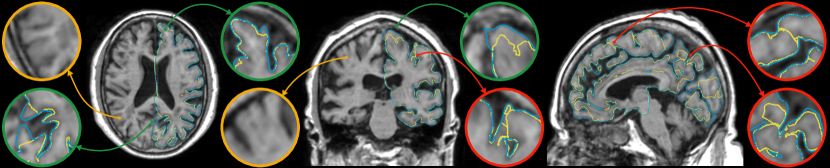

In our experiments, we noticed that CorticalFlow produces more geometrically accurate surfaces than the other methods. On average, it presents better geometric metrics across all the cortical surfaces. In addition, as shown in Figure 3, CorticalFlow errors are smaller () and evenly spread across the surface compared to the other methods. In contrast, NMF and DeepCSR can present substantial errors (). The former has its error spread across the entire surface, while the latter can produce large errors at specific regions.

CorticalFlow is also more robust than the competitors presenting lower error variation across individuals as suggested by the smaller standard deviation of the geometric metrics computed. Interestingly, CorticalFlow is also more robust to MRI artifacts even when the pseudo-ground-truth surface has poor quality. For instance, in Figure 4, CorticalFlow predictions are still plausible for a blurry input MRI while FreeSurfer fails significantly to generate appropriate surfaces for the same input. These examples support our claim that a regular parametrization allows us to reduce non-plausible and non-diffeomorphic predictions that our model cannot learn by construction.